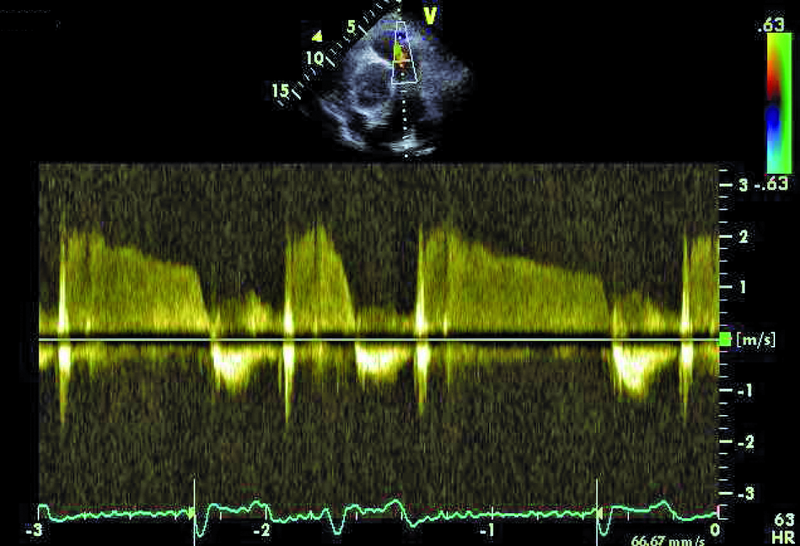

Kobieta, lat 80. Jakie patologie można rozpoznać na rycinach?

4. Niedomykalność zastawki płucnej (ryc. 3).